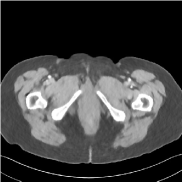

This special case of SUPER corresponds to the case where SUPER excludes the unsupervised regularizer, while only involves the data-fidelity and a supervised regularizer in the MBIR cost, i.e., β=0𝛽0\beta=0 and μ0𝜇0\mu\neq 0. In this case, the proposed SUPER model is similar to a generalized block coordinate descent-based network by replacing a simple denoising autoencoder [28, 29, 30] with a general CNN that forms our supervised regularizer. This SUPER is also similar to the plug-and-play ADMM-Net method except that the inputs to each supervised network are the preceding reconstructions, while plug-and-play ADMM-Net updates inputs to the network (denoiser) based on auxiliary variables in the ADMM algorithm. Here, we used μ=1×106𝜇1superscript106\mu=1\times 10^{6}, which worked well for the plug-and-play ADMM-Net method, for this special case of SUPER. Fig. 7 shows a comparison between plug-and-play ADMM-Net, SUPER without unsupervised regularizers (in both training and testing), and the full SUPER version with ULTRA regularization (β=5×103𝛽5superscript103\beta=5\times 10^{3}, μ=5×105𝜇5superscript105\mu=5\times 10^{5}). All these methods used WavResNet as their denoisers/supervised networks. In this example, SUPER with only a supervised regularizer (SUPER-WRN-β=0𝛽0\beta=0) outperforms the plug-and-play ADMM-Net (ADMM-Net (WRN)) by 1.6 HU RMSE and provides sharper image details. Comparing SUPER-WRN-β=0𝛽0\beta=0 and the full SUPER-WRN-ULTRA scheme, we observe that the latter provides a lower RMSE and higher contrast image features than the former that excludes the unsupervised component. This again shows the effect of the unsupervised ULTRA model (in capturing local image details better with a union of learned transforms) in the SUPER scheme.

Refer to captionADMM-Net (WRN)RMSE = 32.90 HURefer to captionADMM-Net (WRN)RMSE = 32.90 HU

Refer to captionSUPER-WRN-β=0𝛽0\beta=0RMSE = 31.32 HURefer to captionSUPER-WRN-β=0𝛽0\beta=0RMSE = 31.32 HU

Refer to caption SUPER-WRN-ULTRARMSE = 29.74 HURefer to caption SUPER-WRN-ULTRARMSE = 29.74 HU

Refer to caption ReferenceRefer to caption Reference

Figure 7: Reconstructed images of L192 slice 150 with WavResNet plugged ADMM-Net, SUPER-WRN-β=0𝛽0\beta=0 (both training and testing), and SUPER-WRN-ULTRA (β=5×103𝛽5superscript103\beta=5\times 10^{3} in both training and testing), respectively, shown with the reference image.